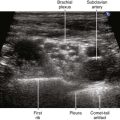

Isotropic means equal in all directions. Anisotropic implies angle dependence. The latter term has been used to indicate the change in amplitude of received echoes from a structure when the angle of insonation is changed. Anisotropy is a discriminating feature between nerves and tendons. Tendons are more anisotropic than nerves, meaning that smaller changes in angle (about 2 degrees) alter the echoes from tendons than the changes in angle (about 10 degrees) that alter the echoes from nerves. The anisotropy of nerves also is important because during interventions it can be challenging to maintain nerve visibility while manipulating the transducer to image the block needle.1 With training, practitioners learn to naturally manipulate the transducer to fill in the received echoes from nerves. The amplitude of the received echoes from peripheral nerves is usually largest when the sound beam is perpendicular to the nerve path. Other structures, such as muscle, also exhibit anisotropy.2

• Anisotropy means that the backscatter echoes from a specimen depend on the directional orientation within the sound field.

• Anisotropy can be quantified by specifying the transducer frequency and the decibel change in backscatter echoes with perpendicular and parallel orientation of the specimen.

• Nerves, tendons, and muscle all exhibit anisotropy. Of these structures, tendon echoes are the most sensitive to transducer manipulation.